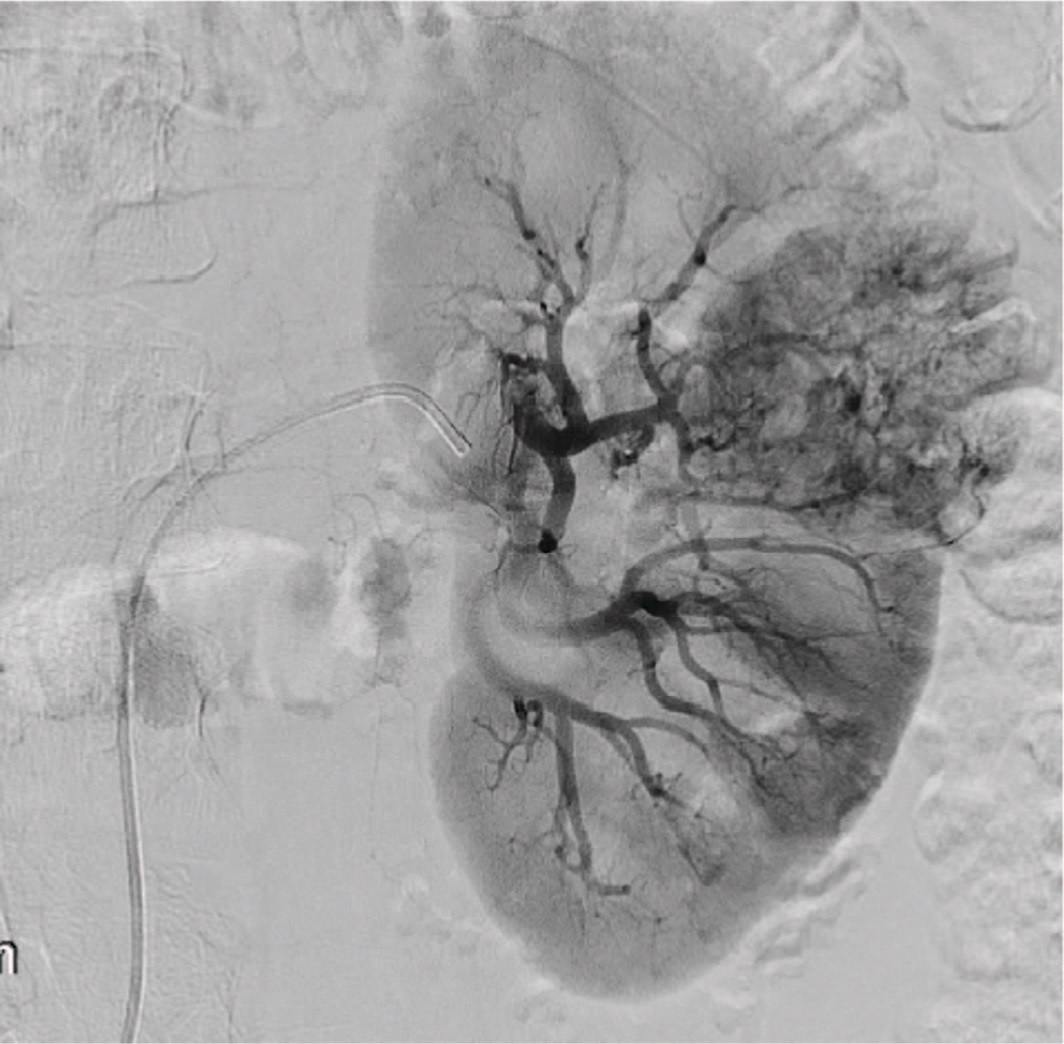

Эмболизации опухолей